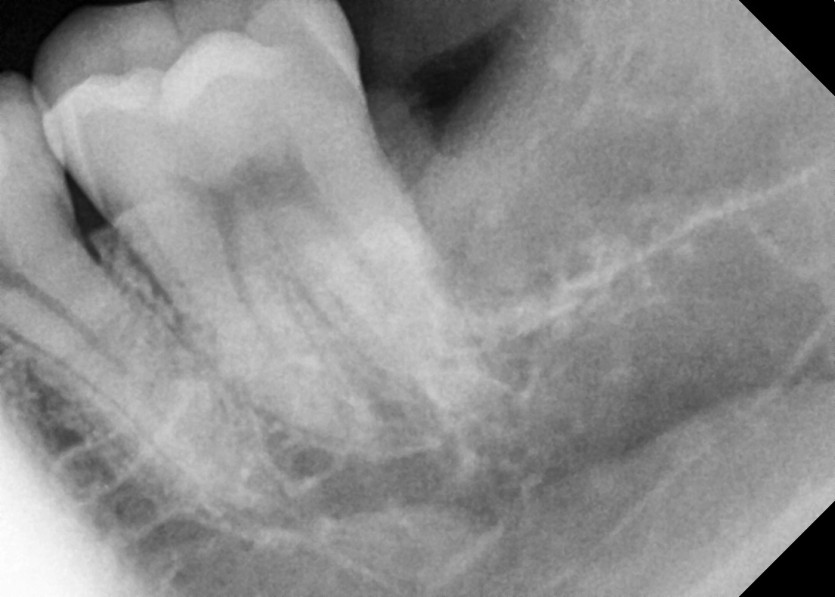

#38 사랑니 발치

구강 외과 전문의가 당일 발치했습니다.